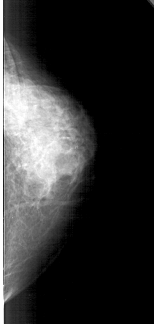

A_1475_1.LEFT_MLO

LEFT_MLO LINES 4651 PIXELS_PER_LINE 2041 BITS_PER_PIXEL 12 RESOLUTION 43.5 OVERLAY